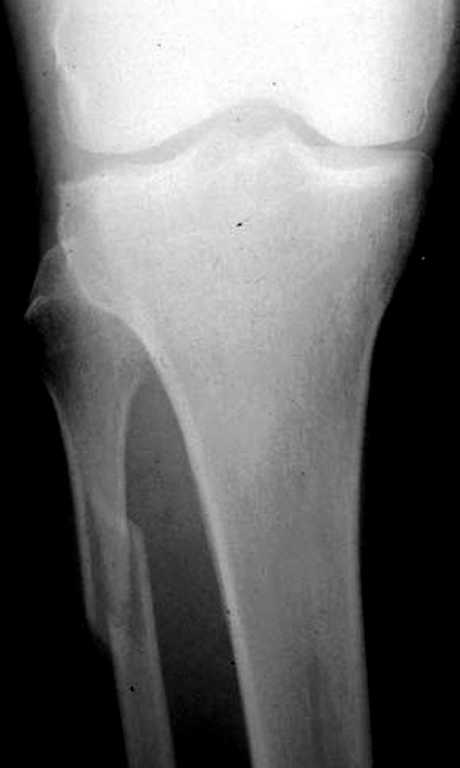

Перелом малоберцовой кости есть, понятно. Но боли в голеностопном суставе! А как вы изучали патологическую подвижность стопы? Есть стрессовые снимки?

Вопрос, который возникает у меня при виде таких снимков,- "Какой механизм травмы?"

Если это прямой удар, то кроме перелома м,б кости и ушиба мягких тканей ничего нет.

Если механизм непрямой, т.е. подворачивание (ротация) стопы, то это повреждение надо классифицировать как нестабильный перелом лодыжек (44 С.2) с повреждением синдесмозных связок.... Да, на обычных рентгенограммах можно

видеть идеальный голеностопный сустав

Надсиндесмозный перелом м\берцовой кости при поврежденнии 44 С. - ДА! но конечно трех недель не ждут.